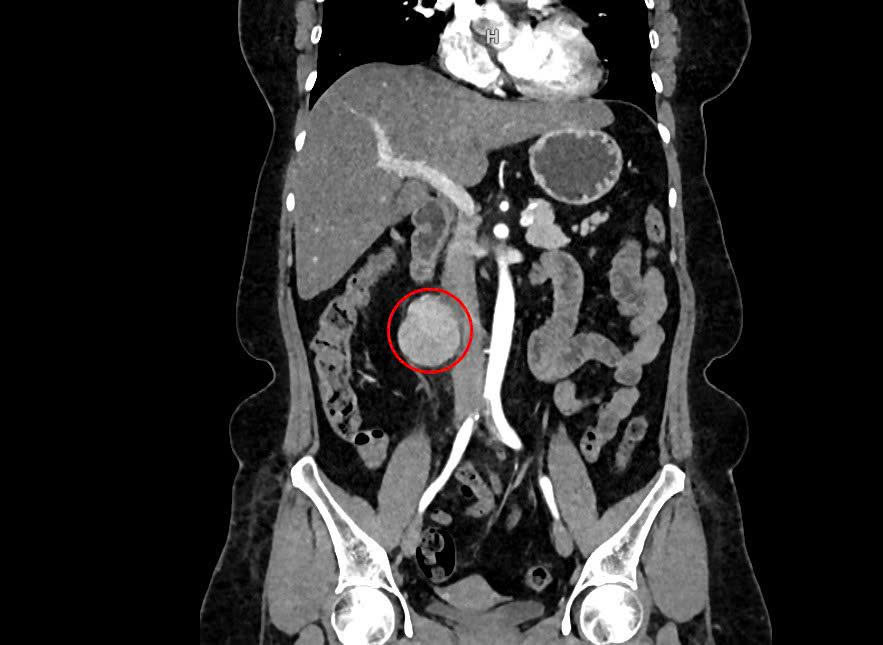

The 6 cm retroperitoneal tumor located near the patient's inferior vena cava. Photo: Tam Anh General Hospital

Dr. Nguyen Tan Cuong, Deputy Head of the Urology Department at Tam Anh General Hospital in Ho Chi Minh City, explained that the tumor was precariously positioned in front of the iliopsoas muscle, adjacent to the inferior vena cava, and near the spine. It was suspected to have originated from the nerve sheath.

Retroperitoneal tumors, like Tan’s, often grow large before causing noticeable symptoms. Located deep within the body, these tumors may present with vague abdominal pain, a palpable mass, digestive issues, or unexplained weight loss. In Tan's case, the tumor was discovered incidentally during a routine check-up, as she experienced no pain or other symptoms.